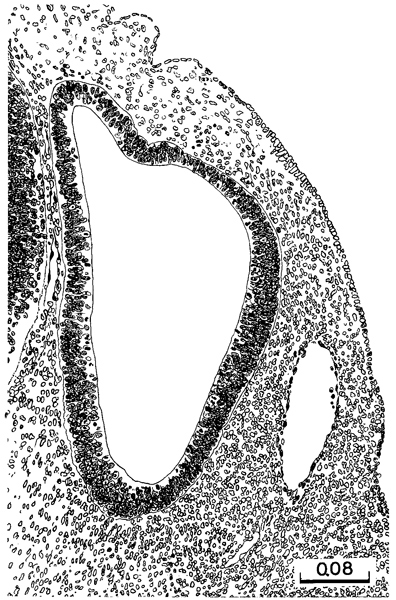

Fig. 14-9. Sections of the eye selected as typical of stage 14, arranged in order of the indentation of the lens disc. Discarded material within the lens pit is shown also in figure 14-7A–C. All drawings are enlarged to the same scale.

In stage 14 the lens disc shows various degrees of indentation, and in the more advanced members of Page 173 the group it is cup-shaped, communicating with the surface by a narrowing pore. There may be a slight variation between the right and left vesicles, but as long as one of them is definitely open to the surface of the embryo, the specimen is included in this stage. The final closure and pinching off occur subsequently.

Sections of the eye, typical of stage 14 and arranged in order of the indentation of the lens ectoderm, are shown in figure 14-9. It will be seen that the lens closely follows the retina in the rate of invagination, and as it does this it becomes partly enclosed by the latter. A significant and constant accompaniment of lens development is the accumulation of a clump of disintegrating cell remnants in the lumen of the lens pit. Photographs of this material are shown in figure 14- 7A–C. From an examination of these and the serial sections themselves one concludes that they are nuclear remnants extruded by the lens ectoderm. The latter is in a state of active cell division, and many of the daughter nuclei can be seen migrating or perhaps being crowded to the surface. Different stages in the emergence of these “unwanted nuclei” and their aggregation in free clumps in the lens depression can be recognized.

A uveocapillary lamina becomes defined. As the retinal disc is invaginated to form the optic cup, the retinal (“choroid”) fissure is delineated. The inverted layer of the optic cup comprises a terminal bar net (the future external limiting membrane), proliferative zone (the mitotic phase), primitive zone (the intermitotic phase), marginal zone, and an internal limiting membrane (O'Rahilly, 1966). The developing cerebral stratum of the retina is closely comparable to the developing cerebral wall (ibid, fig. 8).